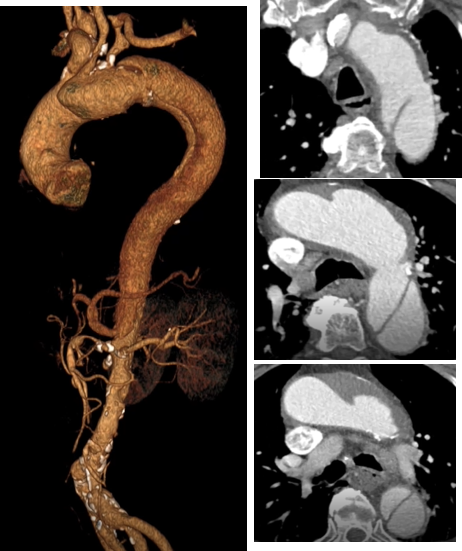

★ 病例2

曹某,男,74岁,“胸背部疼痛10天”入院,主动脉CTA提示:主动脉弓可见多发穿透溃疡,较大之一径约1.2cm。高血压病史10年,血压最高190/80mmHg,糖尿病史12年。

术前CTA

术前

术后

手术用时80分钟